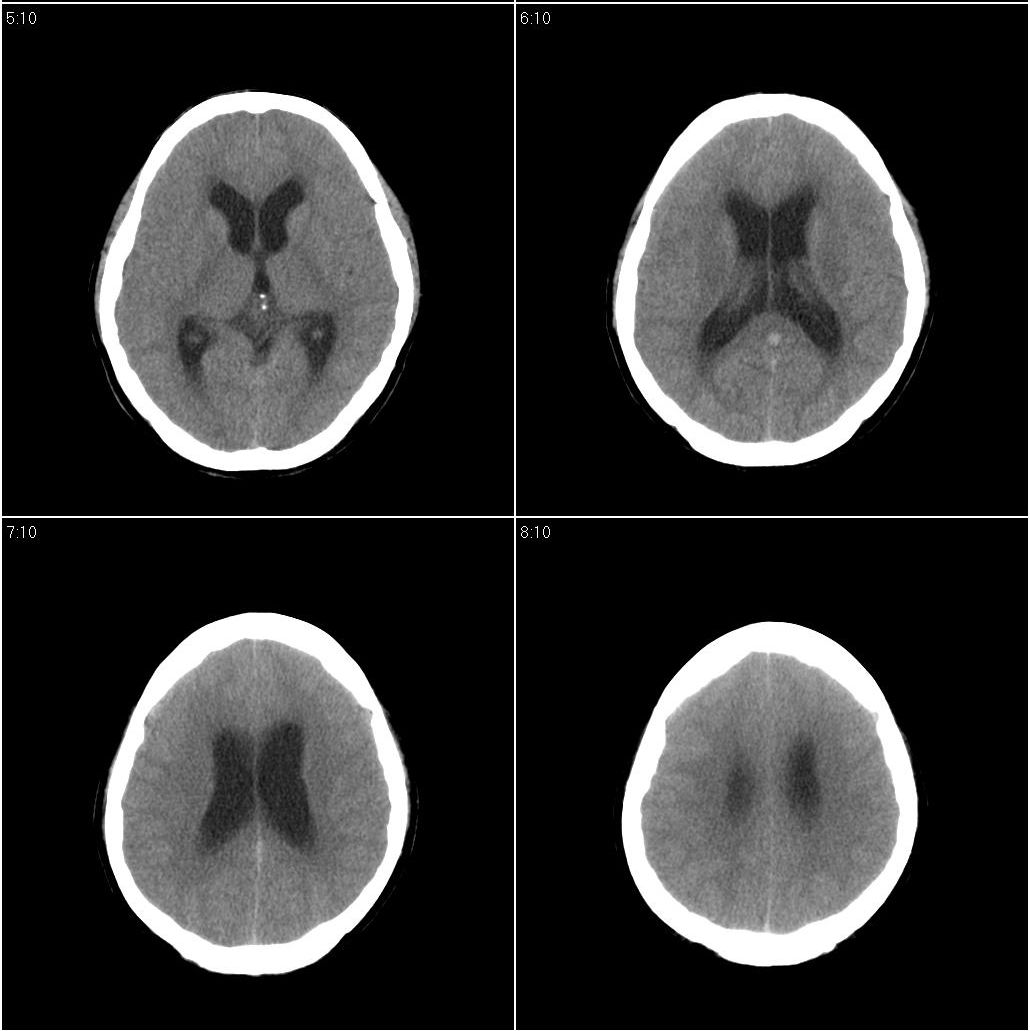

标题: CT16665:男,34岁。近来发现视力不好、眼花。 [打印本页]

标题: CT16665:男,34岁。近来发现视力不好、眼花。

考虑小脑占位性病变,建议ct增强或mri检查。

支持右侧小脑半球占位性病变伴梗阻性脑积水。建议增强,上传骨窗,除外听神经瘤

脑干密度减低,增大,与周围界限不清,四脑室受压显示不清;右侧桥小脑角区似可见稍高密度影;建议行mri检查。

右侧小脑区稍低不均密度占位病变,边界不甚清楚,四脑室受压。建议ct增强或mri进一步检查。

支持右侧小脑半球占位性病变伴梗阻性脑积水。建议增强

1)右侧听神经瘤。2)脑积水(梗阻性)。3)空蝶鞍。